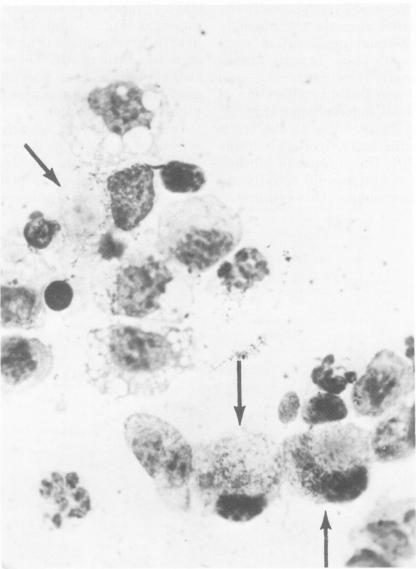

Intraperitoneal (i.p.) infection of BALB/c mice with 1,000 50% mouse lethal doses of the Karp strain of Rickettsia tsutsugamushi was inevitably lethal, and associated pathological alterations were confined to the peritoneal cavity. These included: (i) continuous proliferation of rickettsial organisms in peritoneal macrophages until death; (ii) hepatic granulomas appearing 6 days after infection and increasing in size and number until death; (iii) splenomegaly, resulting principally from proliferation of lymphoid tissue, and (iv) terminal peritonitis. Under two circumstances, i.p. infections with R. tsutsugamushi were not lethal: (i) infection with 100 50% mouse infectious doses of the Gilliam strain, which, in fact, resulted in immune protection against otherwise lethal Karp challenge; and (ii) Karp infection of animals immunized with the Gilliam strain. In both cases, the associated pathological abnormalities were, as with primary Karp infection, restricted to the peritoneal cavity. Also similar was the striking splenomegaly due to lymphoid proliferation, which was particularly prominent in immunized animals. In contrast to primary and lethal Karp infection, however, these infections were characterized by: (i) minimal and transient proliferation of rickettsial organisms in peritoneal macrophages; (ii) disappearance of hepatic granulomas; and (iii) absence of peritonitis. It was concluded that the survival of an animal bearing an i.p. infection of scrub typhus depended on its ability to concentrate a sufficiently vigorous immune response in the peritoneal cavity, resulting in the evolution of rickettsiacidal macrophages capable of suppressing the infection.

用1000个50%小鼠致死剂量的恙虫病东方体卡尔普株对BALB/c小鼠进行腹腔内(i.p.)感染必然致死,相关病理改变局限于腹腔。这些改变包括:(i)立克次体在腹腔巨噬细胞中持续增殖直至死亡;(ii)感染后6天出现肝肉芽肿,其大小和数量不断增加直至死亡;(iii)脾肿大,主要是由于淋巴组织增殖所致;以及(iv)终末期腹膜炎。在两种情况下,恙虫病东方体的腹腔内感染不会致死:(i)用100个50%小鼠感染剂量的吉列姆株进行感染,实际上这会产生针对原本致死的卡尔普株攻击的免疫保护;以及(ii)用吉列姆株免疫的动物感染卡尔普株。在这两种情况下,与原发性卡尔普感染一样,相关的病理异常都局限于腹腔。同样相似的是,由于淋巴组织增殖导致的显著脾肿大,在免疫动物中尤为突出。然而,与原发性和致死性卡尔普感染不同,这些感染的特征是:(i)腹腔巨噬细胞中立克次体的增殖极少且短暂;(ii)肝肉芽肿消失;以及(iii)无腹膜炎。得出的结论是,患有恙虫病腹腔内感染的动物的存活取决于其在腹腔内集中足够强烈的免疫反应的能力,从而导致能够抑制感染的杀立克次体巨噬细胞的进化。